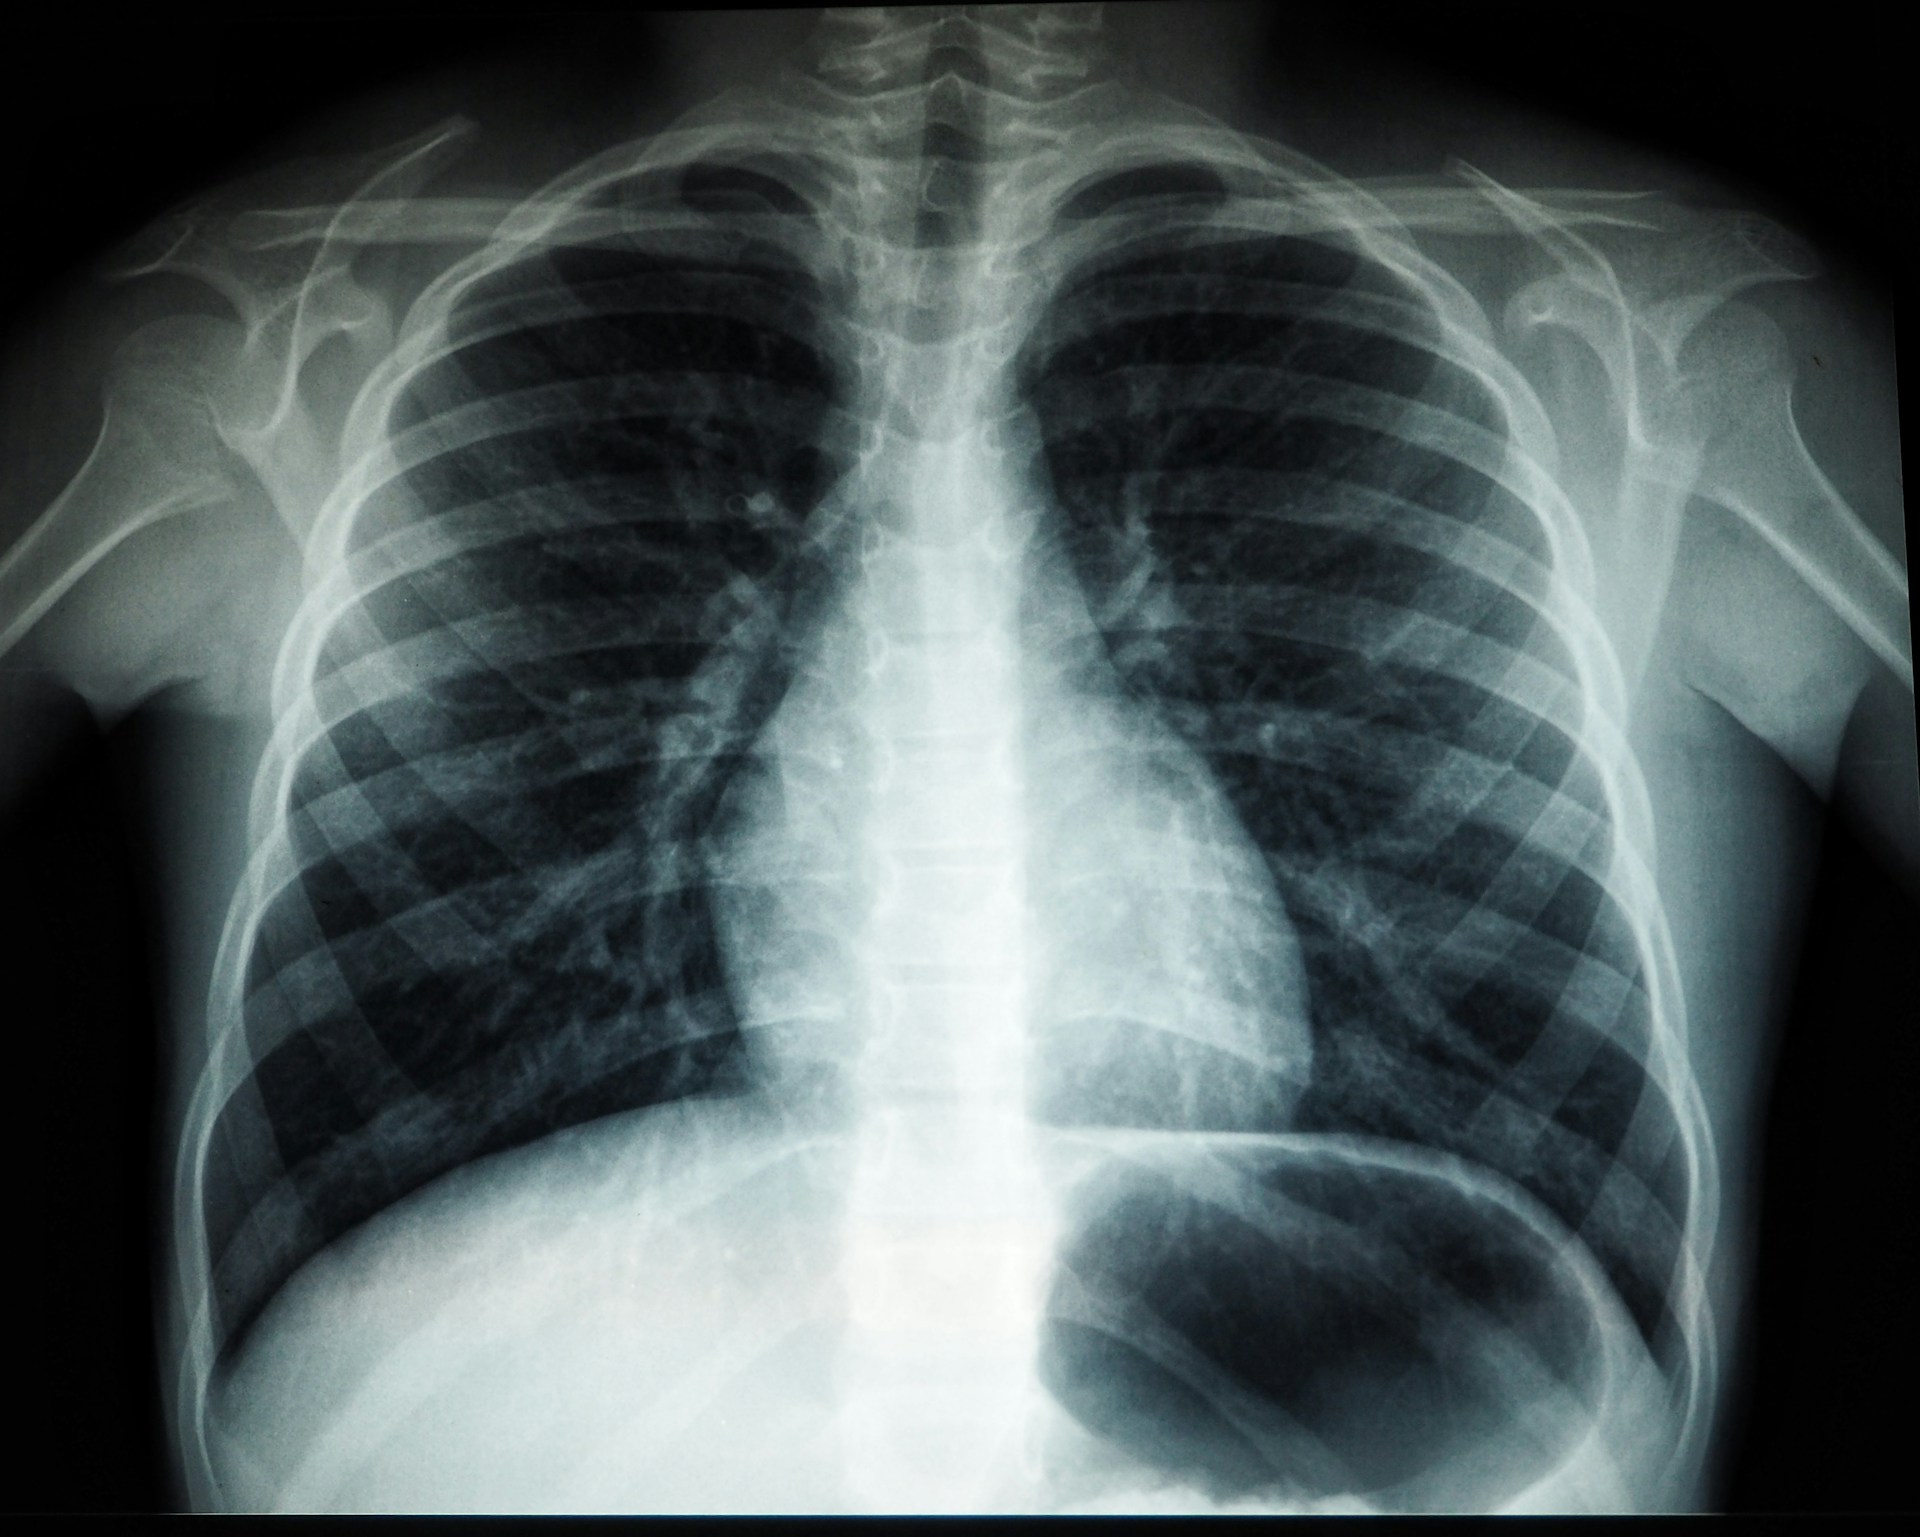

· Pneumonia: Can cause persistent cough, fever, difficulty breathing, and chest pain.